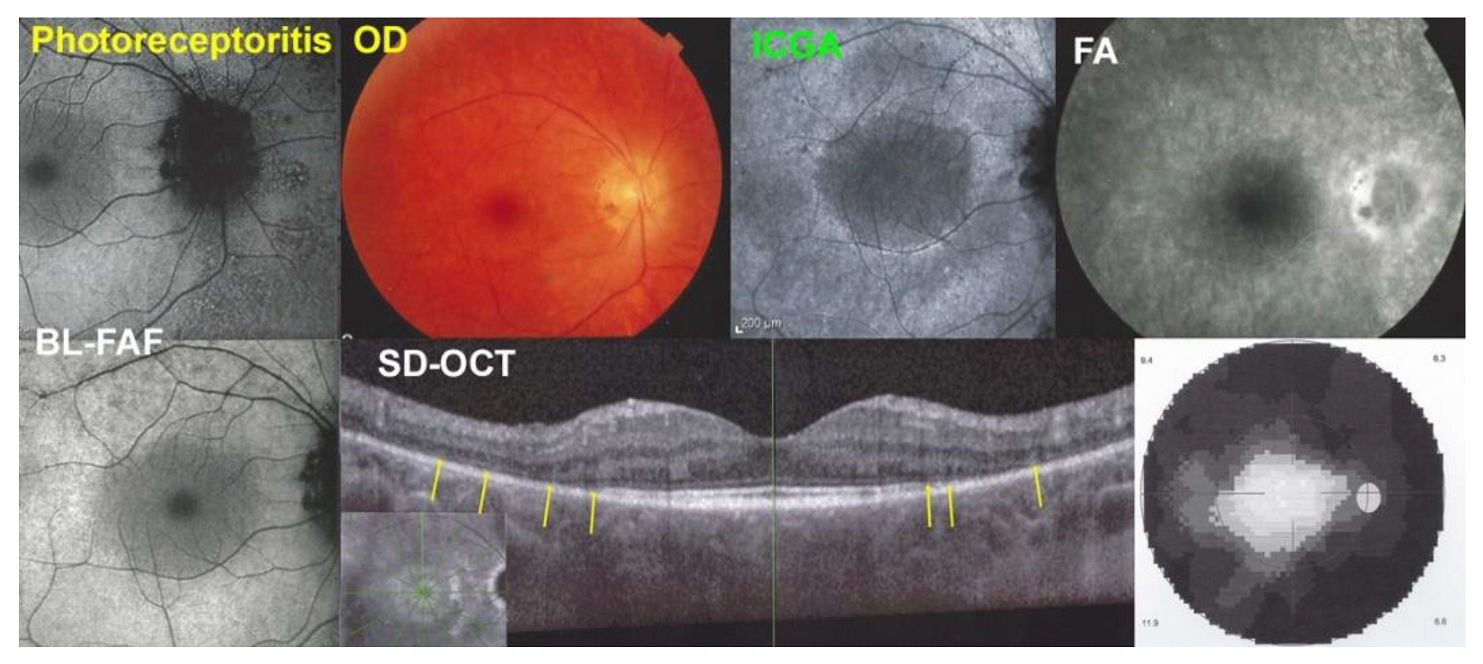

| Fundus | BL-FAF | ICGA | SD-OCT | FA | OCT-A | |

| Photoreceptoritis (n = 5) | Pale halo around fovea 4/5 | Positive-hyperauto-FAF 3/3 | Negative-no-hypofluo 5/5 | Damage/loss of IS/OS 5/5 | no hyperfluor 3/3 | negative 3/3 |

| No non-perfusion | moderate hyperfluor 2/2 |